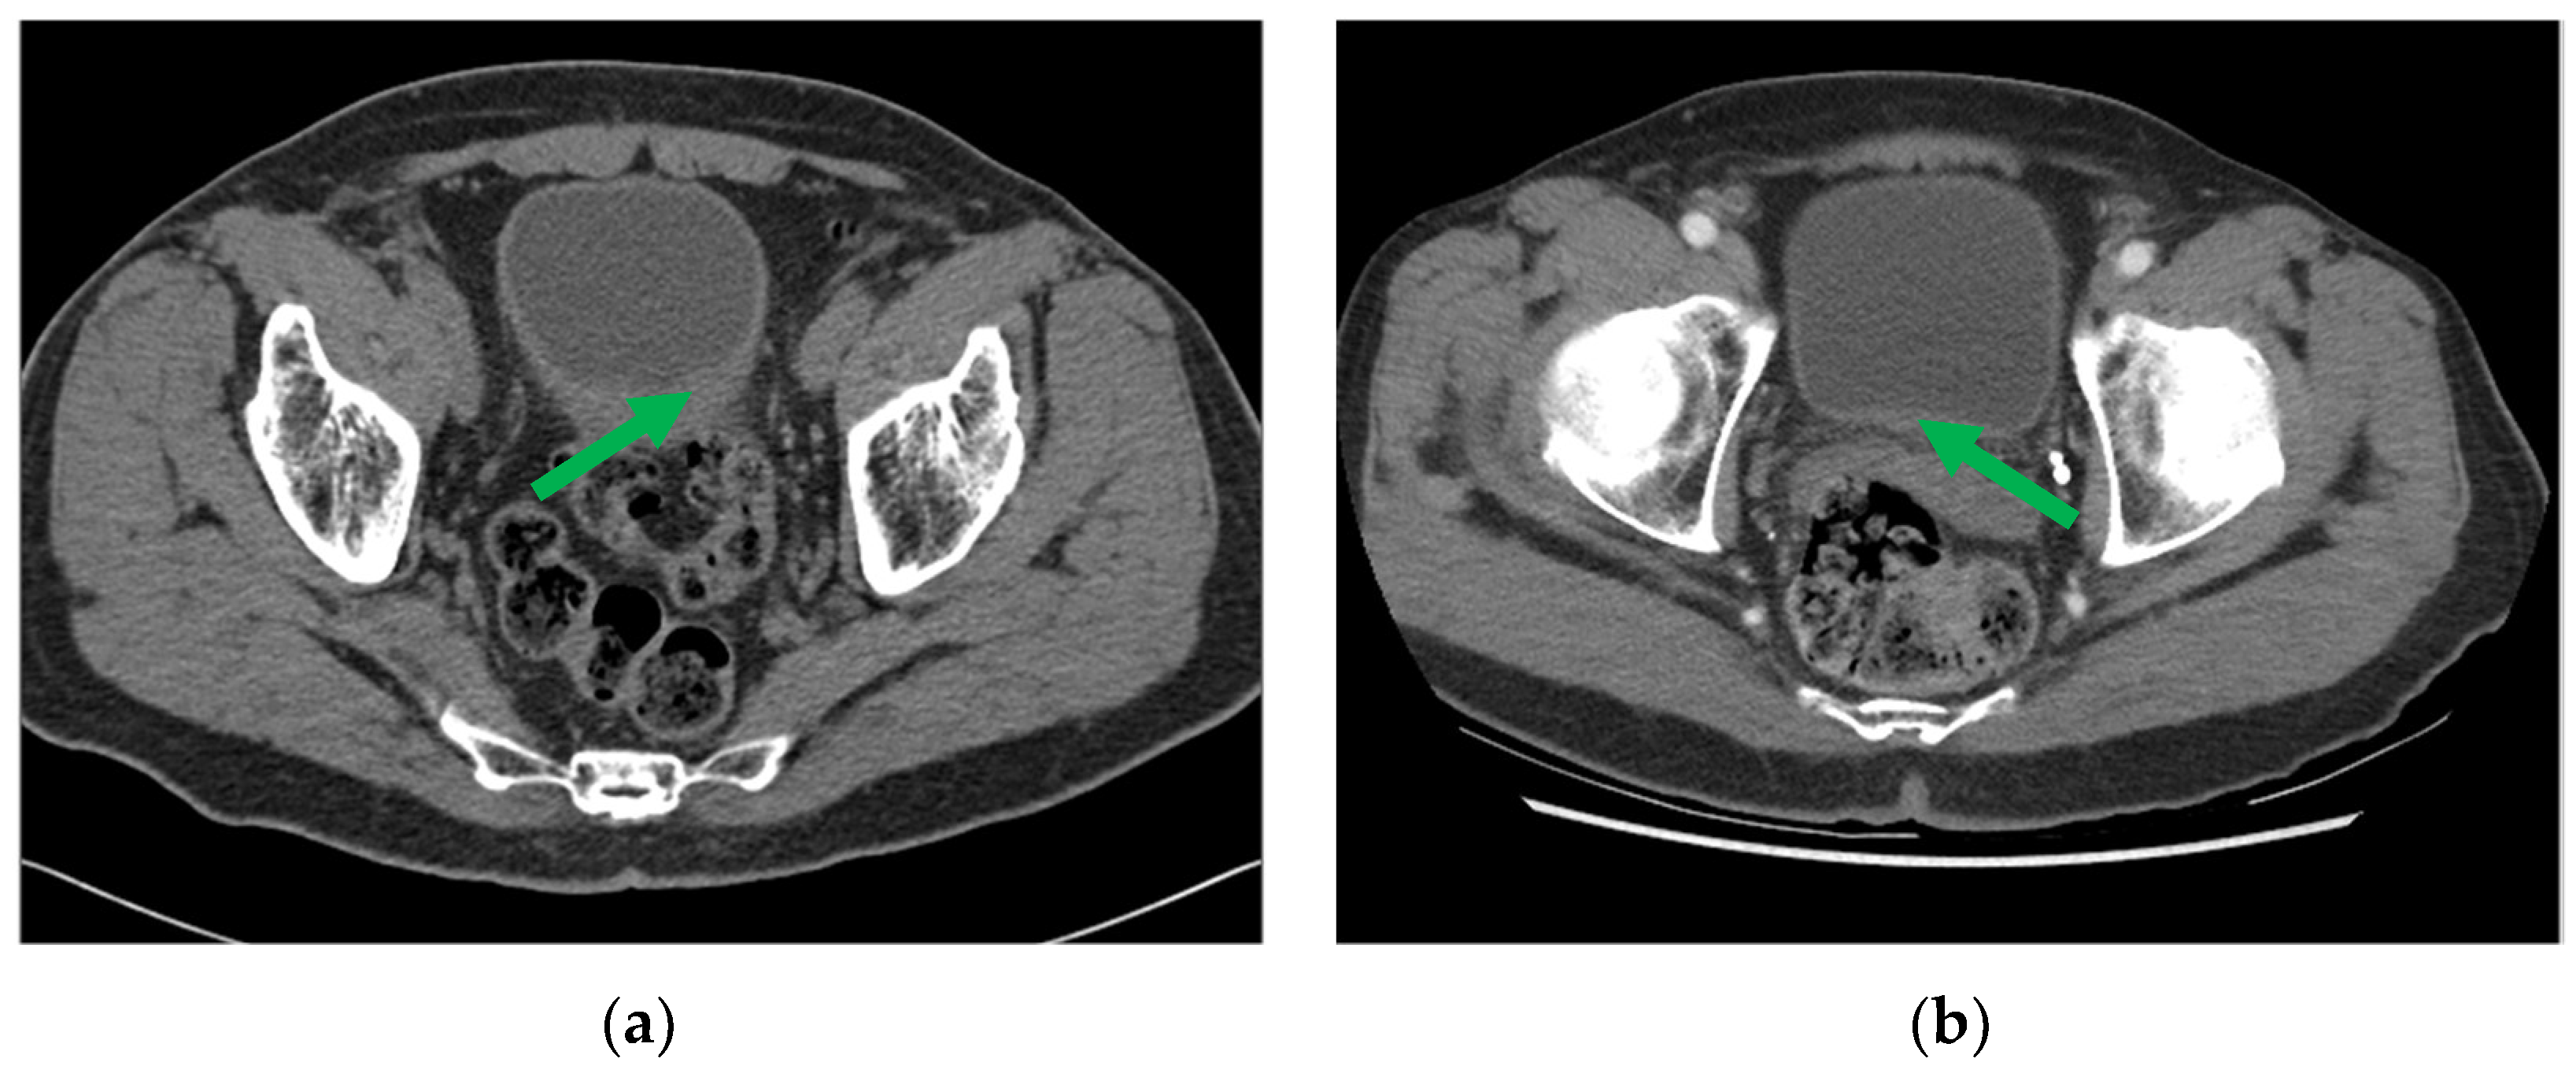

2.2.2. Radiomics (R) Descriptors and Deep Learning (D) Assessment

Radiomics (R) Descriptors:

Deep Learning (D) Assessment: